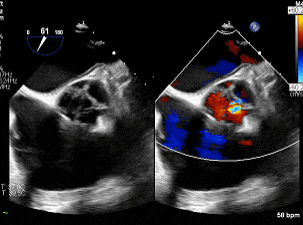

术前主动脉瓣反流,瓣叶钙化,左右交界融合

(食道中段主动脉瓣短轴切面)

6.主动脉瓣环径约3.17cm,窦部内径约4.40cm,升主动脉内径约4.38cm。三维超声示主动脉瓣稍增厚,回声稍增强,呈斜裂二叶活动,左右冠瓣可见一个融合回声,开放自如,大量反流。

1.主动脉瓣二叶式畸形(Type 1型):主动脉瓣重度关闭不全,主动脉根部及升主动脉增宽;2.左心增大,左室整体收缩功能正常范围;3.三尖瓣少量反流。